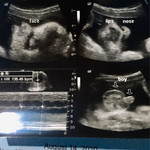

Hello momshies! Mababa na po bah? @38wks and 2days na po..Due date ko na po sa September 15..sana makaraos nah.☺️ang hirap na kasi at ang bigat.